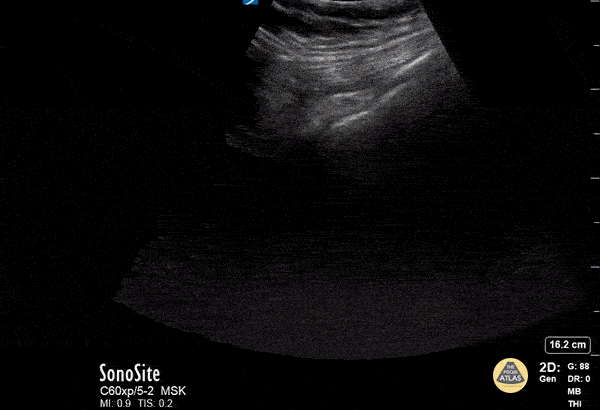

This lung ultrasound shows a "light beam" artifact, a single shining band-form from a regular pleura that appears and disappears with spontaneous respirations. Note also the presence of A-lines. This is highly specific of early COVID-19 infection as described by Volpicelli. Image courtesy of David Hansen, DO & Therese Mead, DO, RDMS, FACEP Central Michigan University Twitter handle: @davidbhansen